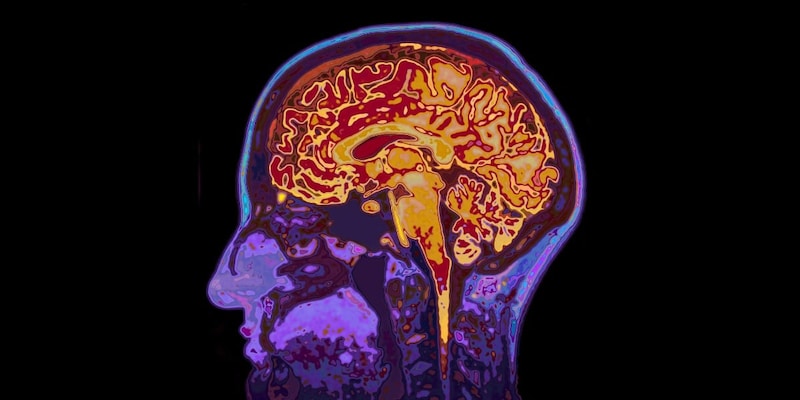

体のどこかにあるがんがシスタチンCというタンパク質をたくさん分泌し、それが血液を流れて脳に入りこみ、TREM2というスイッチを通してミクログリアのゴミ掃除を強めます。

その結果としてアミロイドβのプラークが減り、記憶力もある程度守られる──という流れが、マウスの実験でかなりはっきりと示唆されました。

それに対して、シスタチンCはすでにできてしまったプラークにくっつき、ミクログリアのTREM2を通じて「今あるゴミ山をどう片づけるか」に働きかけます。